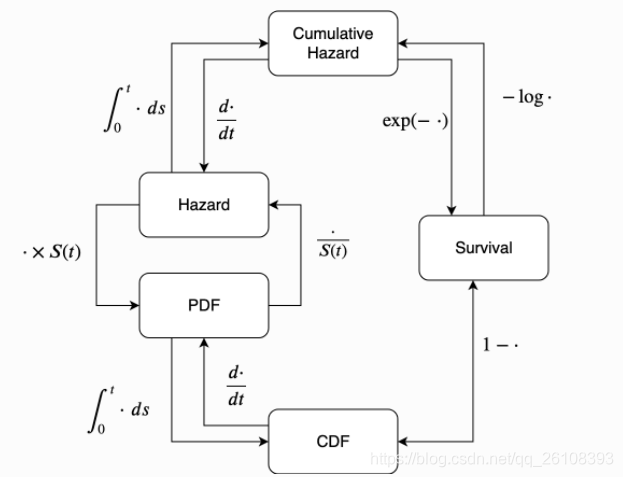

其中的积分部分有一个更为一般的名称,我们称 为累积风险函数。

为累积风险函数。

这张图表示了这些函数之间的关系。